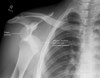

X-ray : 어깨 전방 탈구(Anterior shoulder dislocation)

어깨 탈구가 의심되는 모든 환자에서 일반 외상 시리즈 검사(AP, lateral view를 포함)를 시행해야 합니다.

탈구의 유무와 그 방향이 명확하지 않으면 axillary view를 촬영합니다.

탈구의 방향과 상완골두의 압박골절, 관절와 골절 및 탈구와 연관된 결절부의 골절 등을 확인합니다.